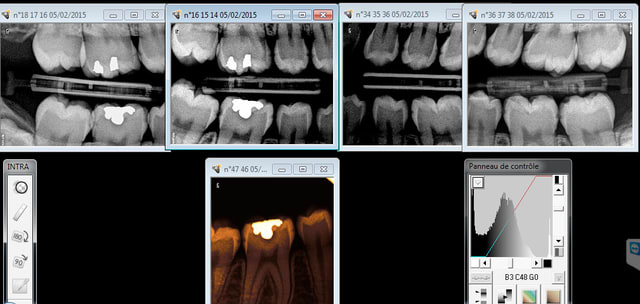

Cas concret. Patiente de 14 ans venant pour la première fois. Sillons infiltrés, je lui fais 5 radios qui révèlent en plus des débuts de caries proximales ( si mon fils présentait ce genre d'image un jour c'est" ICON "sous digue direct mais vu que "c'est pas remboursé" meme pas la peine d'en parler !) . Je commet l'erreur de la soigner d'entrée de jeu (Sous anesthésie, avec moult explications) la maman étant qualifiée par la suite de "très désagréable " à l'accueil par l'assistante.